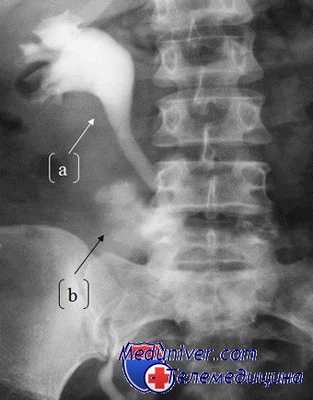

Выбор между хирургическим обследованием и выжидательной тактикой в тех случаях, когда во время операции выявляется недооцененное по степени тяжести повреждение почки, проблематичен. Одни авторы рекомендуют повреждения неустановленного типа исследовать во время операции, другие предлагают более гибкий подход. Если нет рентгенологических данных, то принятию правильного решения может способствовать интраоперационная внутривенная пиелография. Методика проведения данного исследования предполагает болюсное введение йодсодержащего контрастного вещества (2 мл/кг веса) и рентгенологический контроль его экскреции в течение первых 10 минут.

Выявленные существенные изменения в анатомии рассматривают в качестве подтверждающих признаков значительного разрушения паренхимы или повреждения собирательной системы, и в таких случаях может оказаться полезным открытое обследование. При внешней сохранности почки возможен выбор в пользу наблюдения с проведением в послеоперационном периоде КТ-сканирования для более точного отображения имеющихся повреждений. Кроме того, некоторые авторы относят к немаловажным критериям размер паранефральной гематомы.